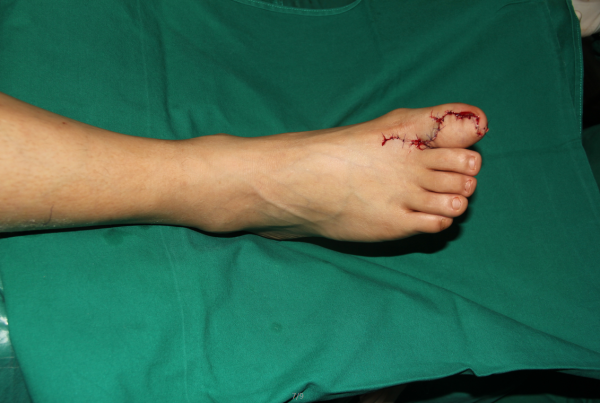

玉米机伤右足复合组织缺损,腓骨皮瓣修复,术后12天,伤口愈合良好,今日出院清创后

设计